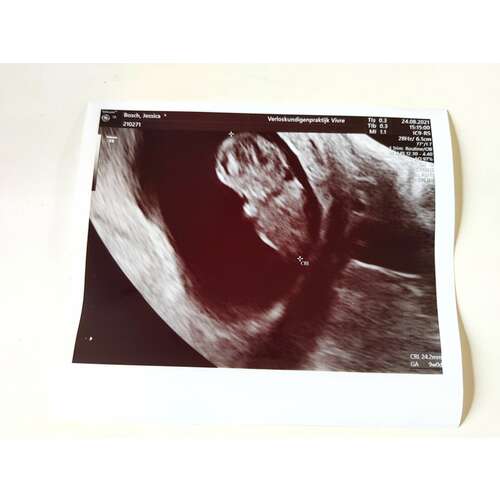

Mijn echo van afgelopen maandag bij 7+4. Helemaal onderin gelegen met het hoofdje rechts, twee ‘stompjes’ die uit moeten groeien tot armpjes. Daarboven het vruchtzakje. Zo bijzonder hoe ze dat allemaal al kunnen zien! Ik ben benieuwd naar de volgende echo.